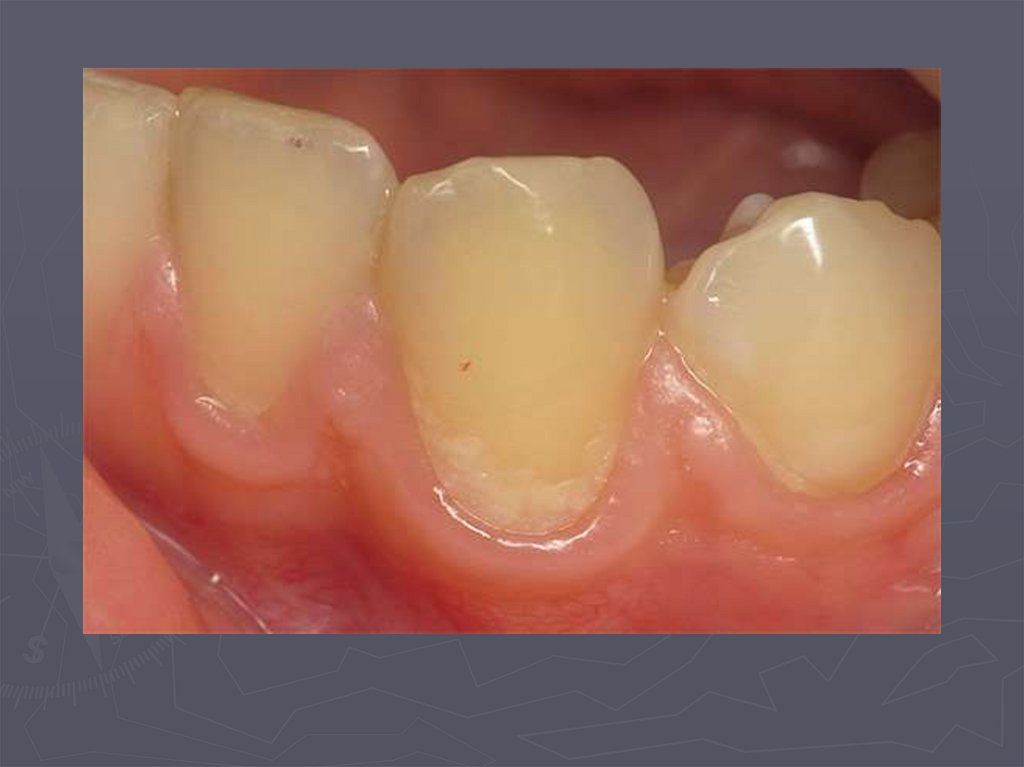

Начальный кариес (кариес в стадии пятна)

19. КЛИНИЧЕСКАЯ КАРТИНА НАЧАЛЬНОГО КАРИЕСА при компенсированной форме:

► заболевание протекает бессимптомно;

► участок поражения может быть покрыт зубным

налетом;

► в участке поражения пятно меловидное или

пигментированное;

► эмаль пятна матовая;

► поверхность пятна гладкая, плотная;

► зондирование безболезненно;

► на температурные раздражители не реагирует.

20. КЛИНИЧЕСКАЯ КАРТИНА НАЧАЛЬНОГО КАРИЕСА при декомпенсированной форме:

►пятно белого или светло-коричневого

цвета;

► пятно не имеет четких границ;

► эмаль пятна тусклая;

► поверхность пятна шероховатая ;

►при зондировании эмаль неплотная.